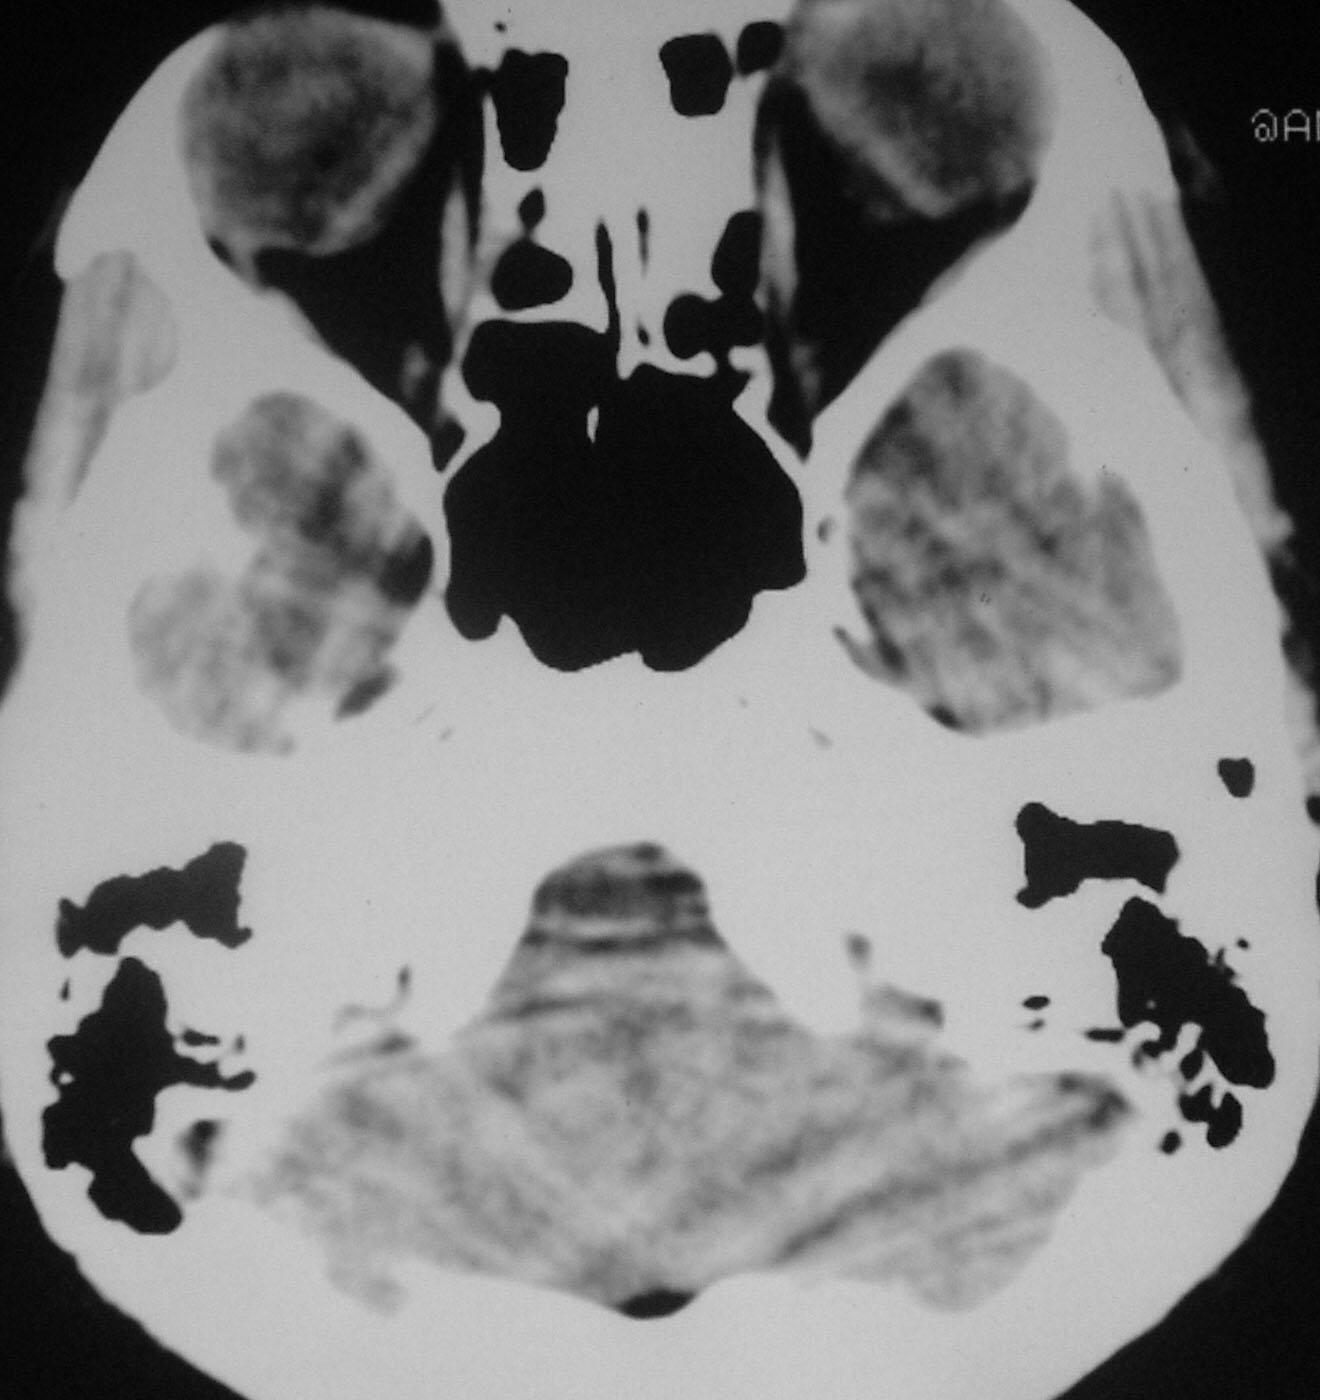

以下是引用余辉在2007-4-28 19:55:00的发言:[br]血管畸形?增强一下

以下是引用jw-830在2007-4-28 20:22:00的发言:[br]考虑血管畸形可能建议增强

以下是引用ysxyy在2007-4-29 21:14:00的发言:[br]像是假像,如果不放心可以偿试一下:[br]你用听眦线为基线扫一下,再用听眶线扫一下,就是说用不同的角度扫同一个地方;[br]看看有无变化,是不是有相同或相似的表现,即可鉴别;